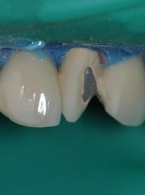

Dobór koloru wypełnienia w praktyce stomatologicznej

Od wielu lat jestem stomatologiem dziecięcym i bardzo często leczę zęby po urazie. Zawsze mam jednak wątpliwości, gdy wykonuję rekonstrukcję kompozytową zębów przednich, czy dobrze dobrałam kolor wypełnienia. Czy jest może jakaś nowoczesna metoda doboru koloru lub urządzenie, które byłoby pomocne w mojej praktyce?